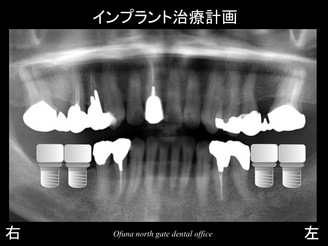

以下のレントゲンは初診時になります。

下顎の左右奥歯(2歯づつの合計4歯欠損)が欠損しています。

そこで、以下のような治療計画になりました。

骨吸収もほとんどないため、単にインプラントを埋入するだけです。

非常にシンプルな治療計画です。